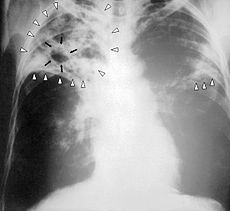

The classic symptoms of active TB infection are a chronic cough with blood-tinged sputum, fever, night sweats, and weight loss (the latter giving rise to the formerly prevalent term "consumption"). Infection of other organs causes a wide range of symptoms. Diagnosis of active TB relies on radiology (commonly chest X-rays), as well as microscopic examination and microbiological culture of body fluids. Diagnosis of latent TB relies on the tuberculin skin test (TST) and/or blood tests. Treatment is difficult and requires administration of multiple antibiotics over a long period of time. Social contacts are also screened and treated if necessary. Antibiotic resistance is a growing problem in multiple drug-resistant tuberculosis (MDR-TB) infections. Prevention relies on screening programs and vaccination with the bacillus Calmette–Guérin vaccine.

If a tuberculosis infection does become active, it most commonly involves the lungs (in about 90% of cases). Symptoms may include chest pain and a prolonged cough producing sputum. About 25% of people may not have any symptoms (i.e. they remain "asymptomatic"). Occasionally, people may cough up blood in small amounts, and in very rare cases, the infection may erode into the pulmonary artery, resulting in massive bleeding ( Rasmussen's aneurysm). Tuberculosis may become a chronic illness and cause extensive scarring in the upper lobes of the lungs. The upper lung lobes are more frequently affected by tuberculosis than the lower ones. The reason for this difference is not entirely clear. It may be due either to better air flow, or to poor lymph drainage within the upper lungs.

Diagnosing active tuberculosis based merely on signs and symptoms is difficult, as is diagnosing the disease in those who are immunosuppressed. A diagnosis of TB should, however, be considered in those with signs of lung disease or constitutional symptoms lasting longer than two weeks. A chest X-ray and multiple sputum cultures for acid-fast bacilli are typically part of the initial evaluation. Interferon-γ release assays and tuberculin skin tests are of little use in the developing world. IGRA have similar limitations in those with HIV.